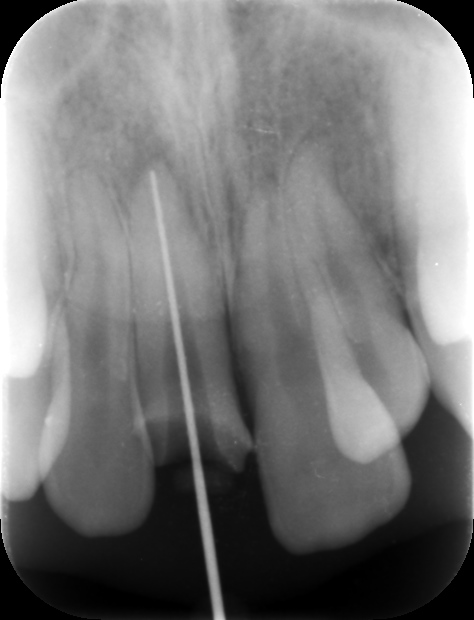

初診時レントゲン。左側中切歯の根尖部は小指頭大の黒いレントゲン透過像を認め、歯髄壊死と診断した。まずは感染根管治療を行うこととした。

ファイル試適。歯根の長さと方向を確認する。

根管内部を完全に清掃・消毒し、バイオセラミックシーラーにて根管充填を行った。根尖部までしっかりと薬が詰まっているのが分かる。